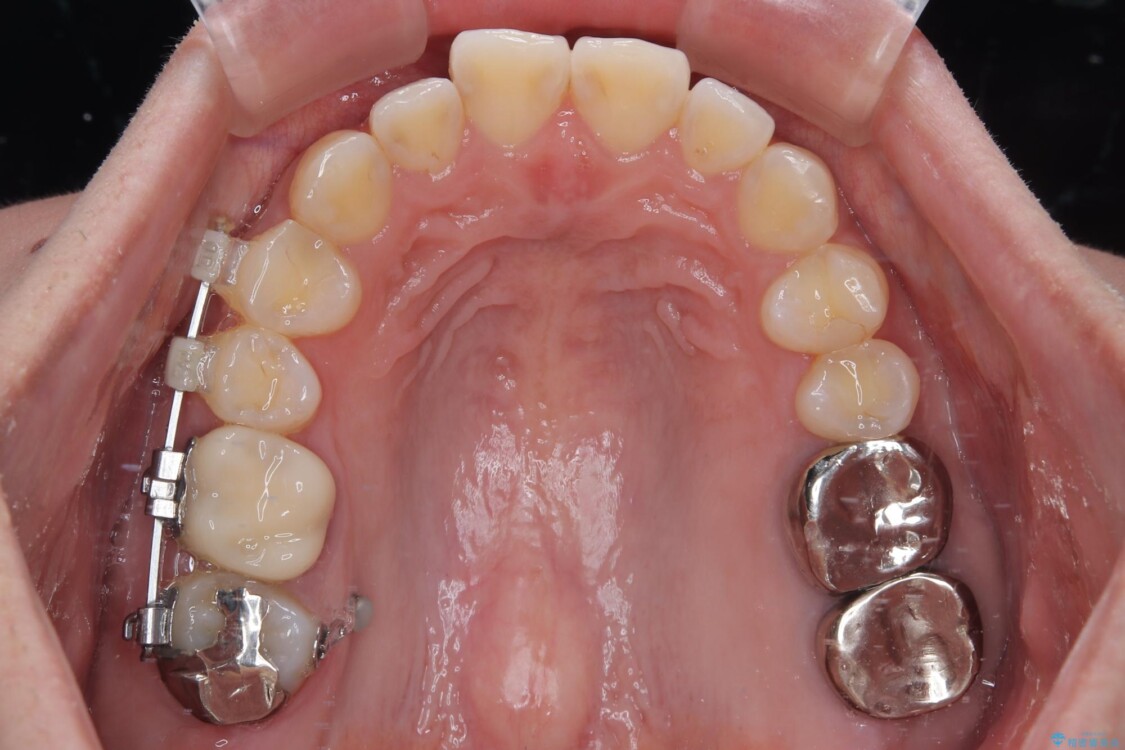

そこで、右上の奥歯に部分的なワイヤーを装着し、さらに矯正用アンカースクリュー(TADs)を併用することで、挺出した歯を圧下(歯を元の高さに戻す動き)させ、下顎にインプラントを埋入するための十分な垂直的スペースを確保しました。

→ この装置は部分的な矯正で、前歯など見える位置にワイヤーがかかることはなく、見た目を気にすることなく、普段通りの生活を送りながら治療を進めることができました。

• 挺出歯を圧下してスペースを確保!目立たない部分矯正で下顎大臼歯にインプラント治療を実現 治療途中画像